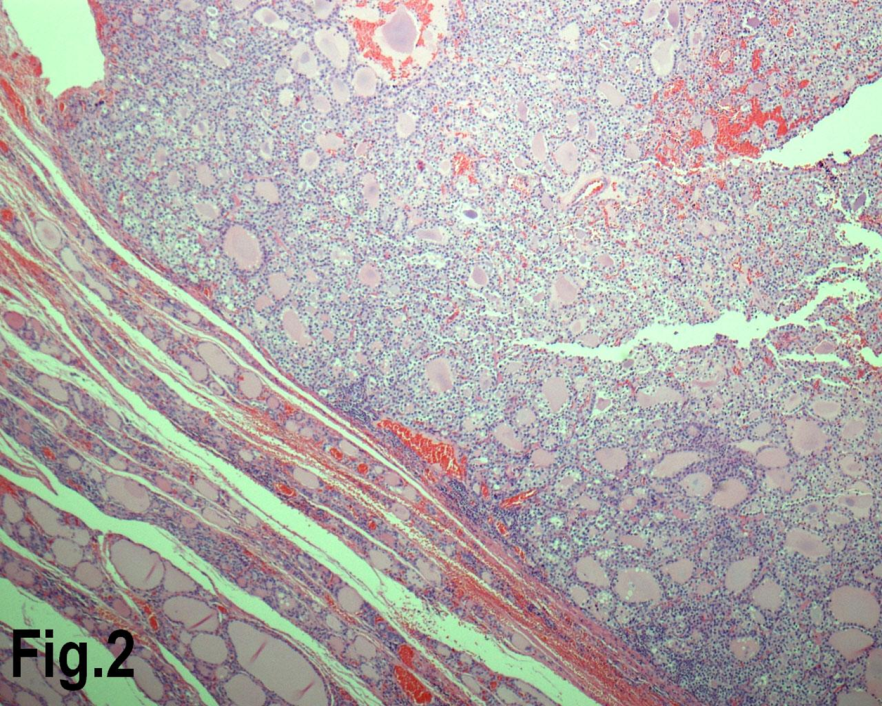

Figure 2.Low power view showing a follicular adenoma. (Hematoxylin & eosin, original magnification ×200).

Solitary benign adenomas were found in 23 cases, the peak frequency was fourth and fifth decade. Female accounted for 12 cases (70.5%) for follicular adenoma (Figure 2) and 3 cases (50%) for Hurthle cell adenoma. Thyroid malignancy and it was reported in 62 cases. Papillary carcinoma (Figure 3) was the most common type of thyroid malignancy found in 44 cases (71%) followed by follicular carcinoma (9.6%) (Figure 4), medullary carcinoma (1.6) and poorly differentiated carcinoma (1.6%) (Table 3). The peak incidence for patients with thyroid malignancy in this series was third decade and male to female ratio was 3.7:1.